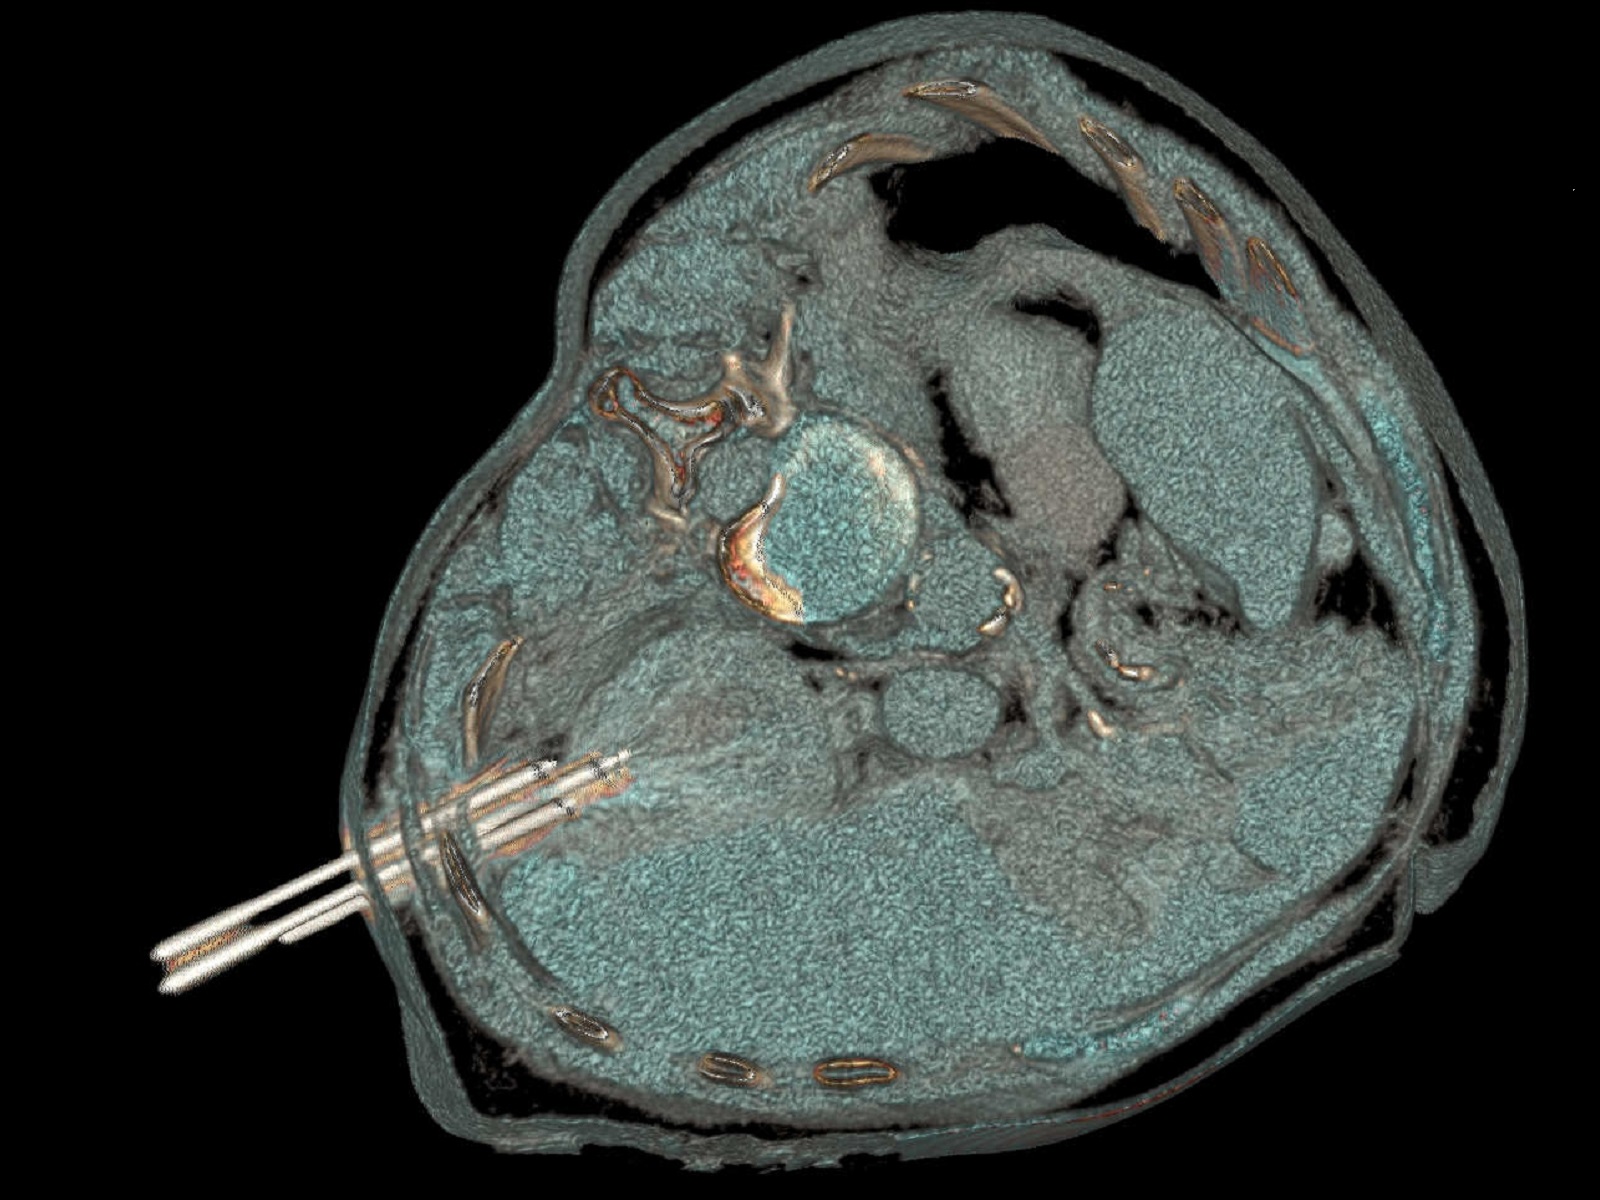

zielony_igly.jpg – trzy igły wbite w guz, obrazy tomograficzne;

igly_w_guzie.jpg – Guz nakłuty trzema igłami pod kontrolą tomografii komputerowe